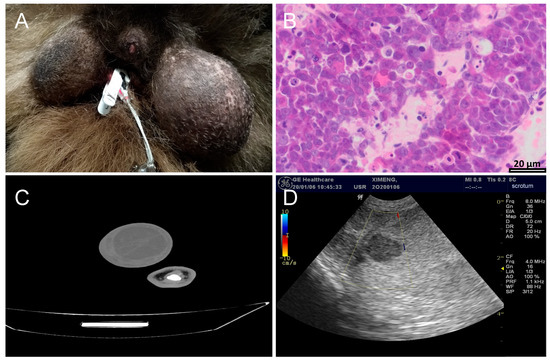

2. Overview of Testicular Cancer in Giant Pandas

4. Diagnosis of Testicular Tumor in Giant Pandas

- Zhang, T.; Zhong, G.; Tang, Z.; Dong, G. Diagnosis and surgical management of testicular seminoma in captive giant panda (Ailuropoda melanoleuca). Vet. Anim. Sci. 2023, 20, 100295. [Google Scholar] [CrossRef]

- Zhu, Y.; Huang, Z.; Li, C.; Li, C.; Wei, M.; Deng, L.; Deng, W.; Zhou, X.; Wu, K.; Yang, B.; et al. Blood mir-331-3p is a potential diagnostic marker for giant panda (Ailuropoda melanoleuca) testicular tumor. BMC Vet. Res. 2024, 20, 515. [Google Scholar] [CrossRef]

- Yijiao, C.; Junhui, A.; Rong, H.; Yuliang, L.; Donghui, W.; Songrui, L.; Tongying, F. Single-cell mRNA sequencing of giant panda (Ailuropoda melanoleuca) seminoma reveals the cellular and molecular characteristics of tumour cells. Vet. Med. Sci. 2024, 10, e1348. [Google Scholar] [CrossRef] [PubMed]